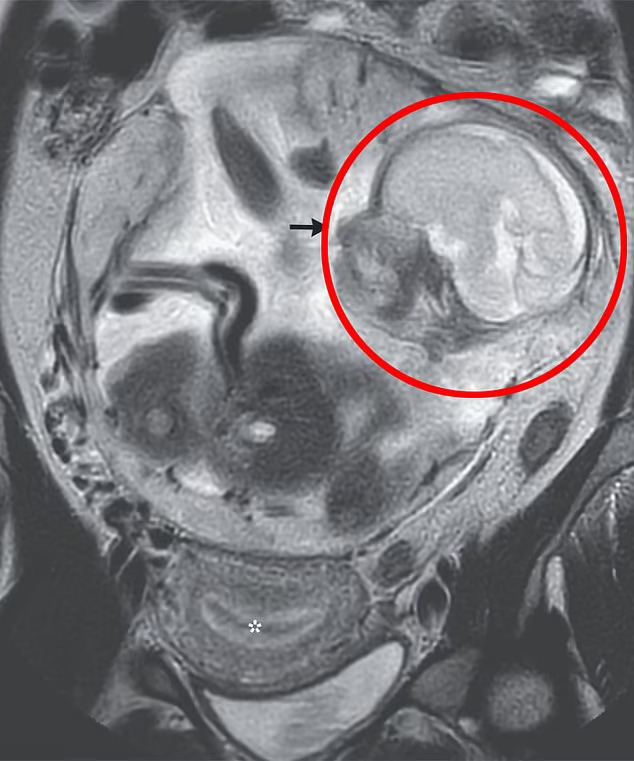

Жената (37) отишла кај лекарите жалејќи се на болка во стомакот која траела 10 дена – како и на надуеност која постепено се влошувала. Скенирањето открило дека „нормално формиран“ фетус расте во нејзината абдоминална празнина – просторот помеѓу желудникот и цревата.

Лекарите и дијагностицирале абдоминална бременост, еден вид ектопична бременост – или бременост надвор од матката – што се јавува во абдоменот. Бебето било во перитонеалната празнина, или во областа каде што се држат виталните органи, со плацентата прикачена на врвот на карлицата.